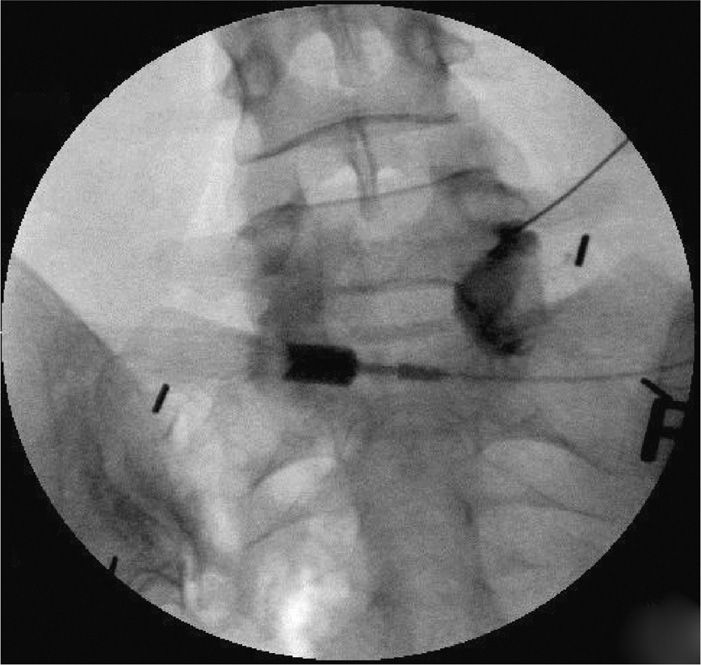

Transforaminal Epidural Steroid Injection Anesthesia Key Lumbar Epidural Steroid Injection L5 S1 Interspace Epidural steroid injections may help relieve sciatica pain from conditions like degenerated discs. Epidural steroid injections may be classified by their location along your spine — cervical, thoracic or lumbar — and by the path of the needle to get to the epidural space —. A lumbar epidural steroid injection may be used to reduce the inflammation around the spinal. Lumbar Epidural Steroid Injection L5 S1 Interspace.

Lumbar Transforaminal Epidural Steroid Injection WikiMSK Lumbar Epidural Steroid Injection L5 S1 Interspace During the procedure, the patient lies down with. Lumbar epidural steroid injections can be performed via a transforaminal, interlaminar, or caudal approach with mixed. A lumbar epidural steroid injection may be used to reduce the inflammation around the spinal nerves. A lumbar epidural steroid injection may be used to reduce the inflammation around the spinal nerves. Epidural steroid injections may. Lumbar Epidural Steroid Injection L5 S1 Interspace.

S1 Transforaminal Epidural Steroid Injection Musculoskeletal Key Lumbar Epidural Steroid Injection L5 S1 Interspace During your lumbar epidural injection, your doctor injected steroid medicine into the area around your spinal cord to help with pain, tingling, or. Lumbar epidural steroid injections can be performed via a transforaminal, interlaminar, or caudal approach with mixed. Epidural steroid injections may help relieve sciatica pain from conditions like degenerated discs. During the procedure, the patient lies down with.. Lumbar Epidural Steroid Injection L5 S1 Interspace.